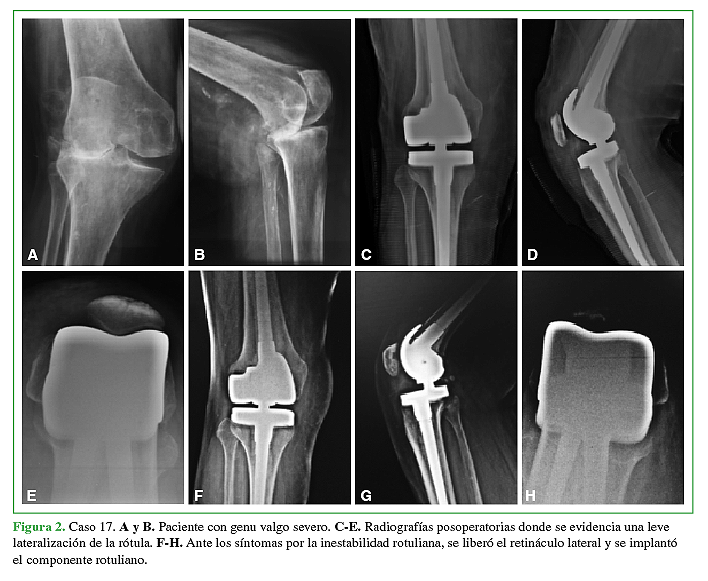

Introducción El objetivo del trabajo es presentar los resultados clínicos y radiológicos a mediano plazo de 34 artroplastías totales de rodilla abisagradas-rotatorias. Materiales y Métodos Estudiamos un grupo de 34 prótesis abisagradas de rodilla. La indicación de una bisagra fue en 10 casos (29.5%) en el escenario de una cirugía primaria y en 24 casos (70.5%) en el escenario de una cirugía de revisión. La edad promedio de la serie fue de 78.5 años (rango de 54 a 85). Resultados El seguimiento promedio fue de 6.5 años (rango de 2 a 12 años). El rango de movilidad conseguido fue 110º de flexión (rango de 70º – 130º) y 5º de extensión (rango de 0º a 20º). El puntaje promedio en el KSS mejoró de 38 en el preoperatorio a 82 en el postoperatorio. En la evaluación radiológica detectamos en 8 (23%) casos líneas radiolúcidas > a 2mm alrededor del componente femoral y/o tibial o alrededor de los vástagos. Cinco de 34 prótesis (14.7%) presentaron complicaciones. En 3 casos (8.9%) se trató de una infección profunda. Dos casos (5.9%) presentaron complicaciones patelo-femorales. La sobrevida de la prótesis libre de revisión a los 6.5 años fue de 94%. Si consideramos el aflojamiento aséptico como causa de revisión la sobrevida fue del 100%. Conclusión Las prótesis abisagradas rotatorias de rodilla modernas presentan buenos resultados funcionales y de alivio del dolor. También se asocian a bajos índices de aflojamiento aséptico a mediano plazo. Sin embargo, las complicaciones sépticas son frecuentes.Descargas